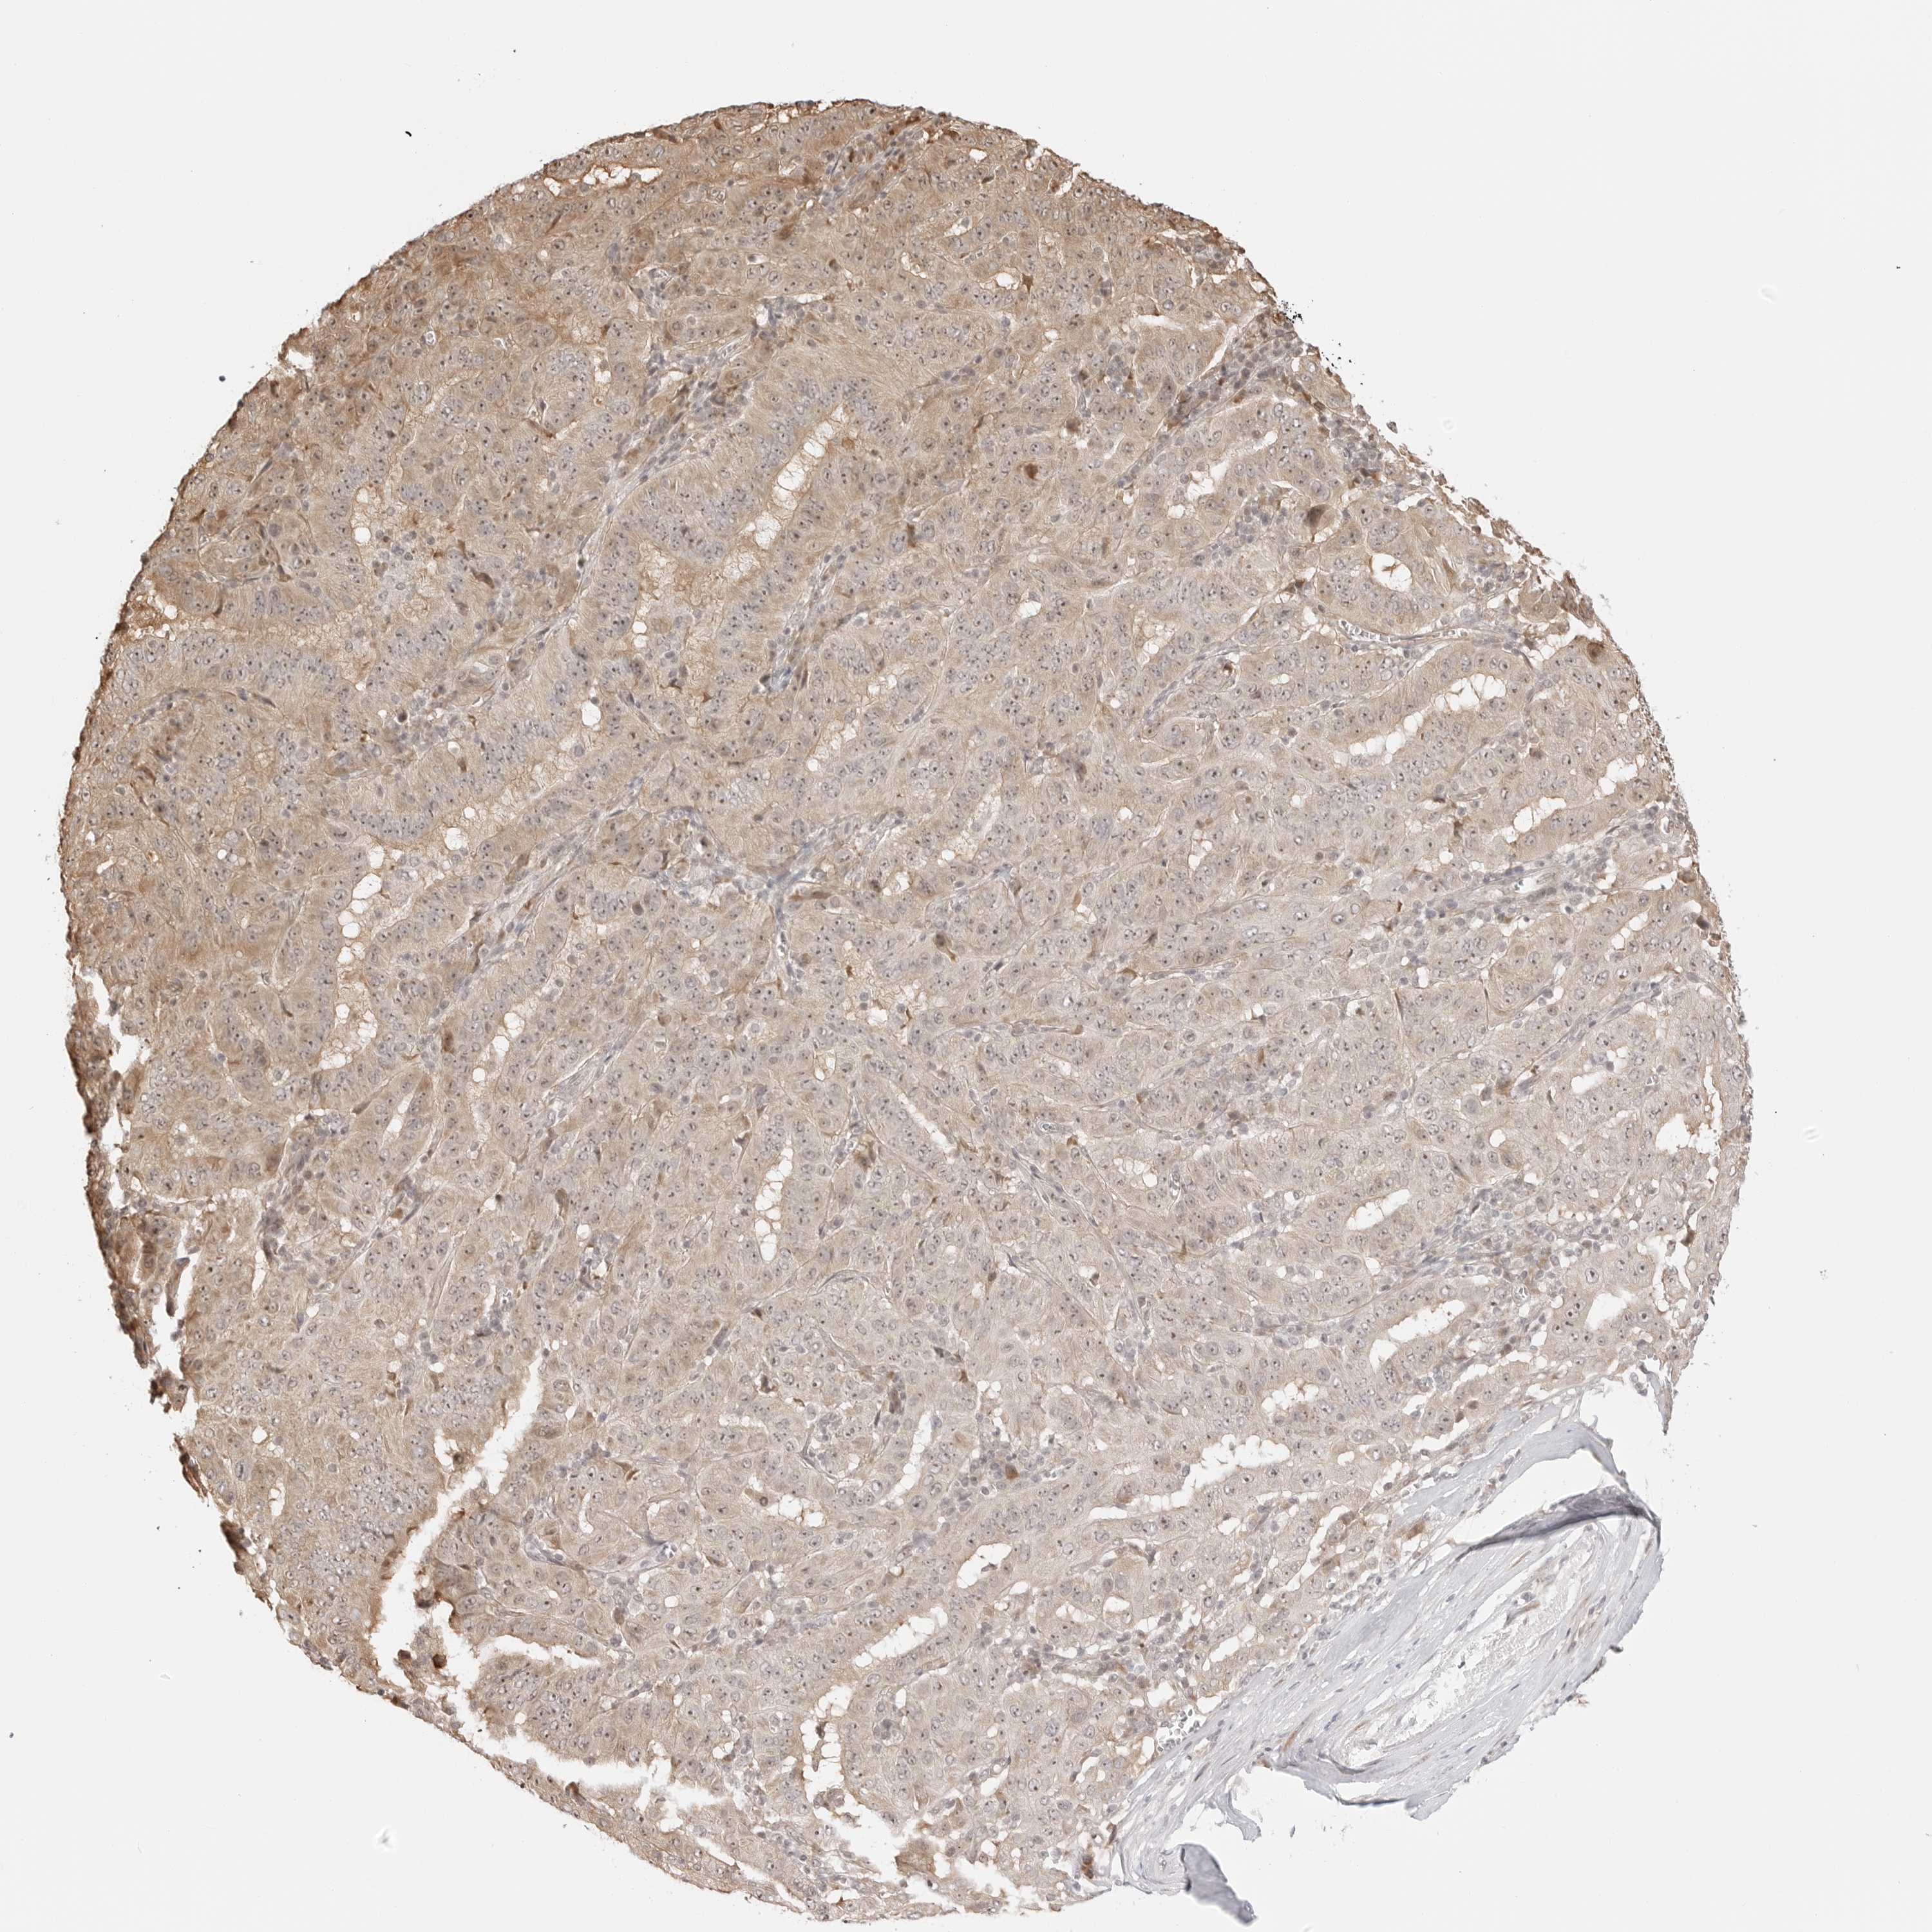

PANCREATIC CANCER - Protein expressioni

A mouse-over function shows sample information and annotation data. Click on an image to view it in a full screen mode. Samples can be filtered based on level of antibody staining by selecting one or several of the following categories: high, medium, low and not detected. The assay and annotation is described here.

Note that samples used for immunohistochemistry by the Human Protein Atlas do not correspond to samples in the TCGA dataset.

Antibody stainingi

Antibody staining in the annotated cell types in the current human tissue is reported as not detected, low, medium, or high, based on conventional immunohistochemistry profiling in selected tissues. This score is based on the combination of the staining intensity and fraction of stained cells.

Each image is clickable and will lead to virtual microscopy that enables deeper exploration of all samples and also displays staining intensity scores, fraction scores and subcellular localization as well as patient and tissue information for each sample.

Antibody HPA013329

Antibody HPA026829

Staining

High

Medium

Low

Not detected

Intensity

Strong

Moderate

Weak

Negative

Quantity

>75%

75%-25%

<25%

None

Location

Nuclear

Cytoplasmic/membranous

Cytoplasmic/membranous,nuclear

Adenocarcinoma, NOS